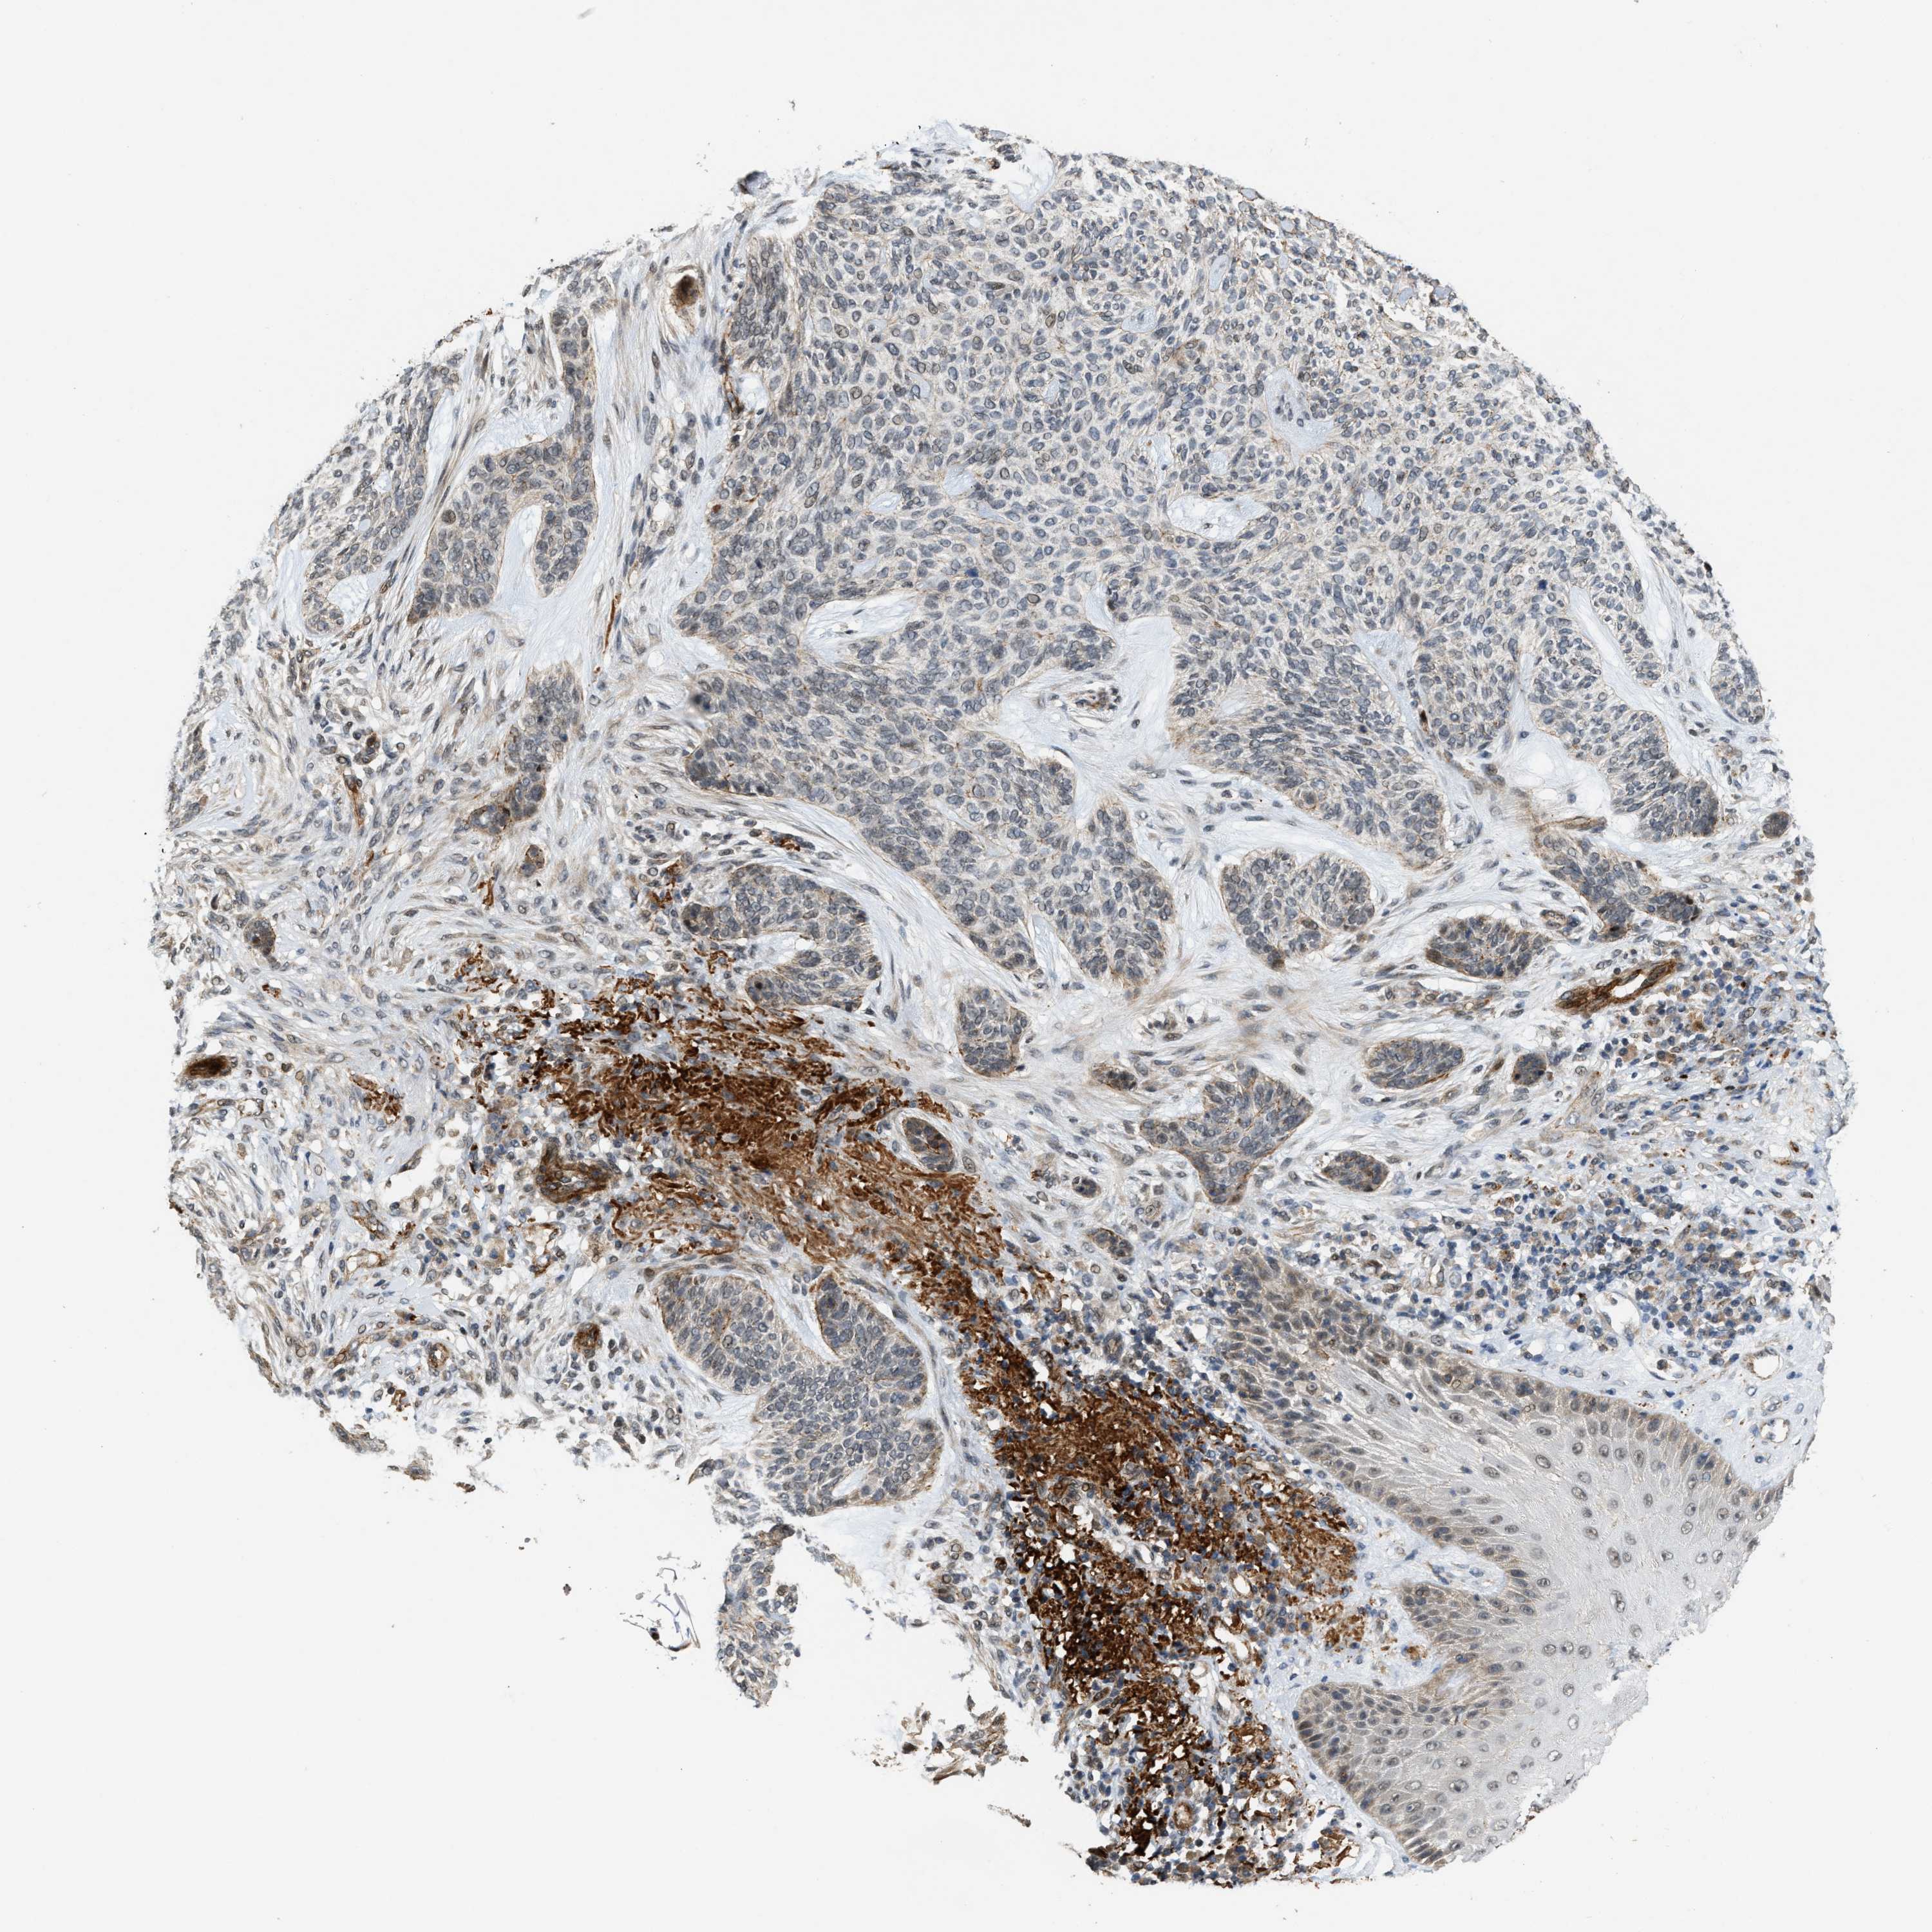

SKIN CANCER - Protein expressioni

A mouse-over function shows sample information and annotation data. Click on an image to view it in a full screen mode. Samples can be filtered based on level of antibody staining by selecting one or several of the following categories: high, medium, low and not detected. The assay and annotation is described here.

Antibody stainingi

Antibody staining in the annotated cell types in the current human tissue is reported as not detected, low, medium, or high, based on conventional immunohistochemistry profiling in selected tissues. This score is based on the combination of the staining intensity and fraction of stained cells.

Each image is clickable and will lead to virtual microscopy that enables deeper exploration of all samples and also displays staining intensity scores, fraction scores and subcellular localization as well as patient and tissue information for each sample.

Antibody HPA020880

Staining

High

Intensity

Strong

Quantity

>75%

Location

Nuclear

Basal cell carcinoma

Squamous cell carcinoma, NOS

Squamous cell carcinoma, metastatic, NOS